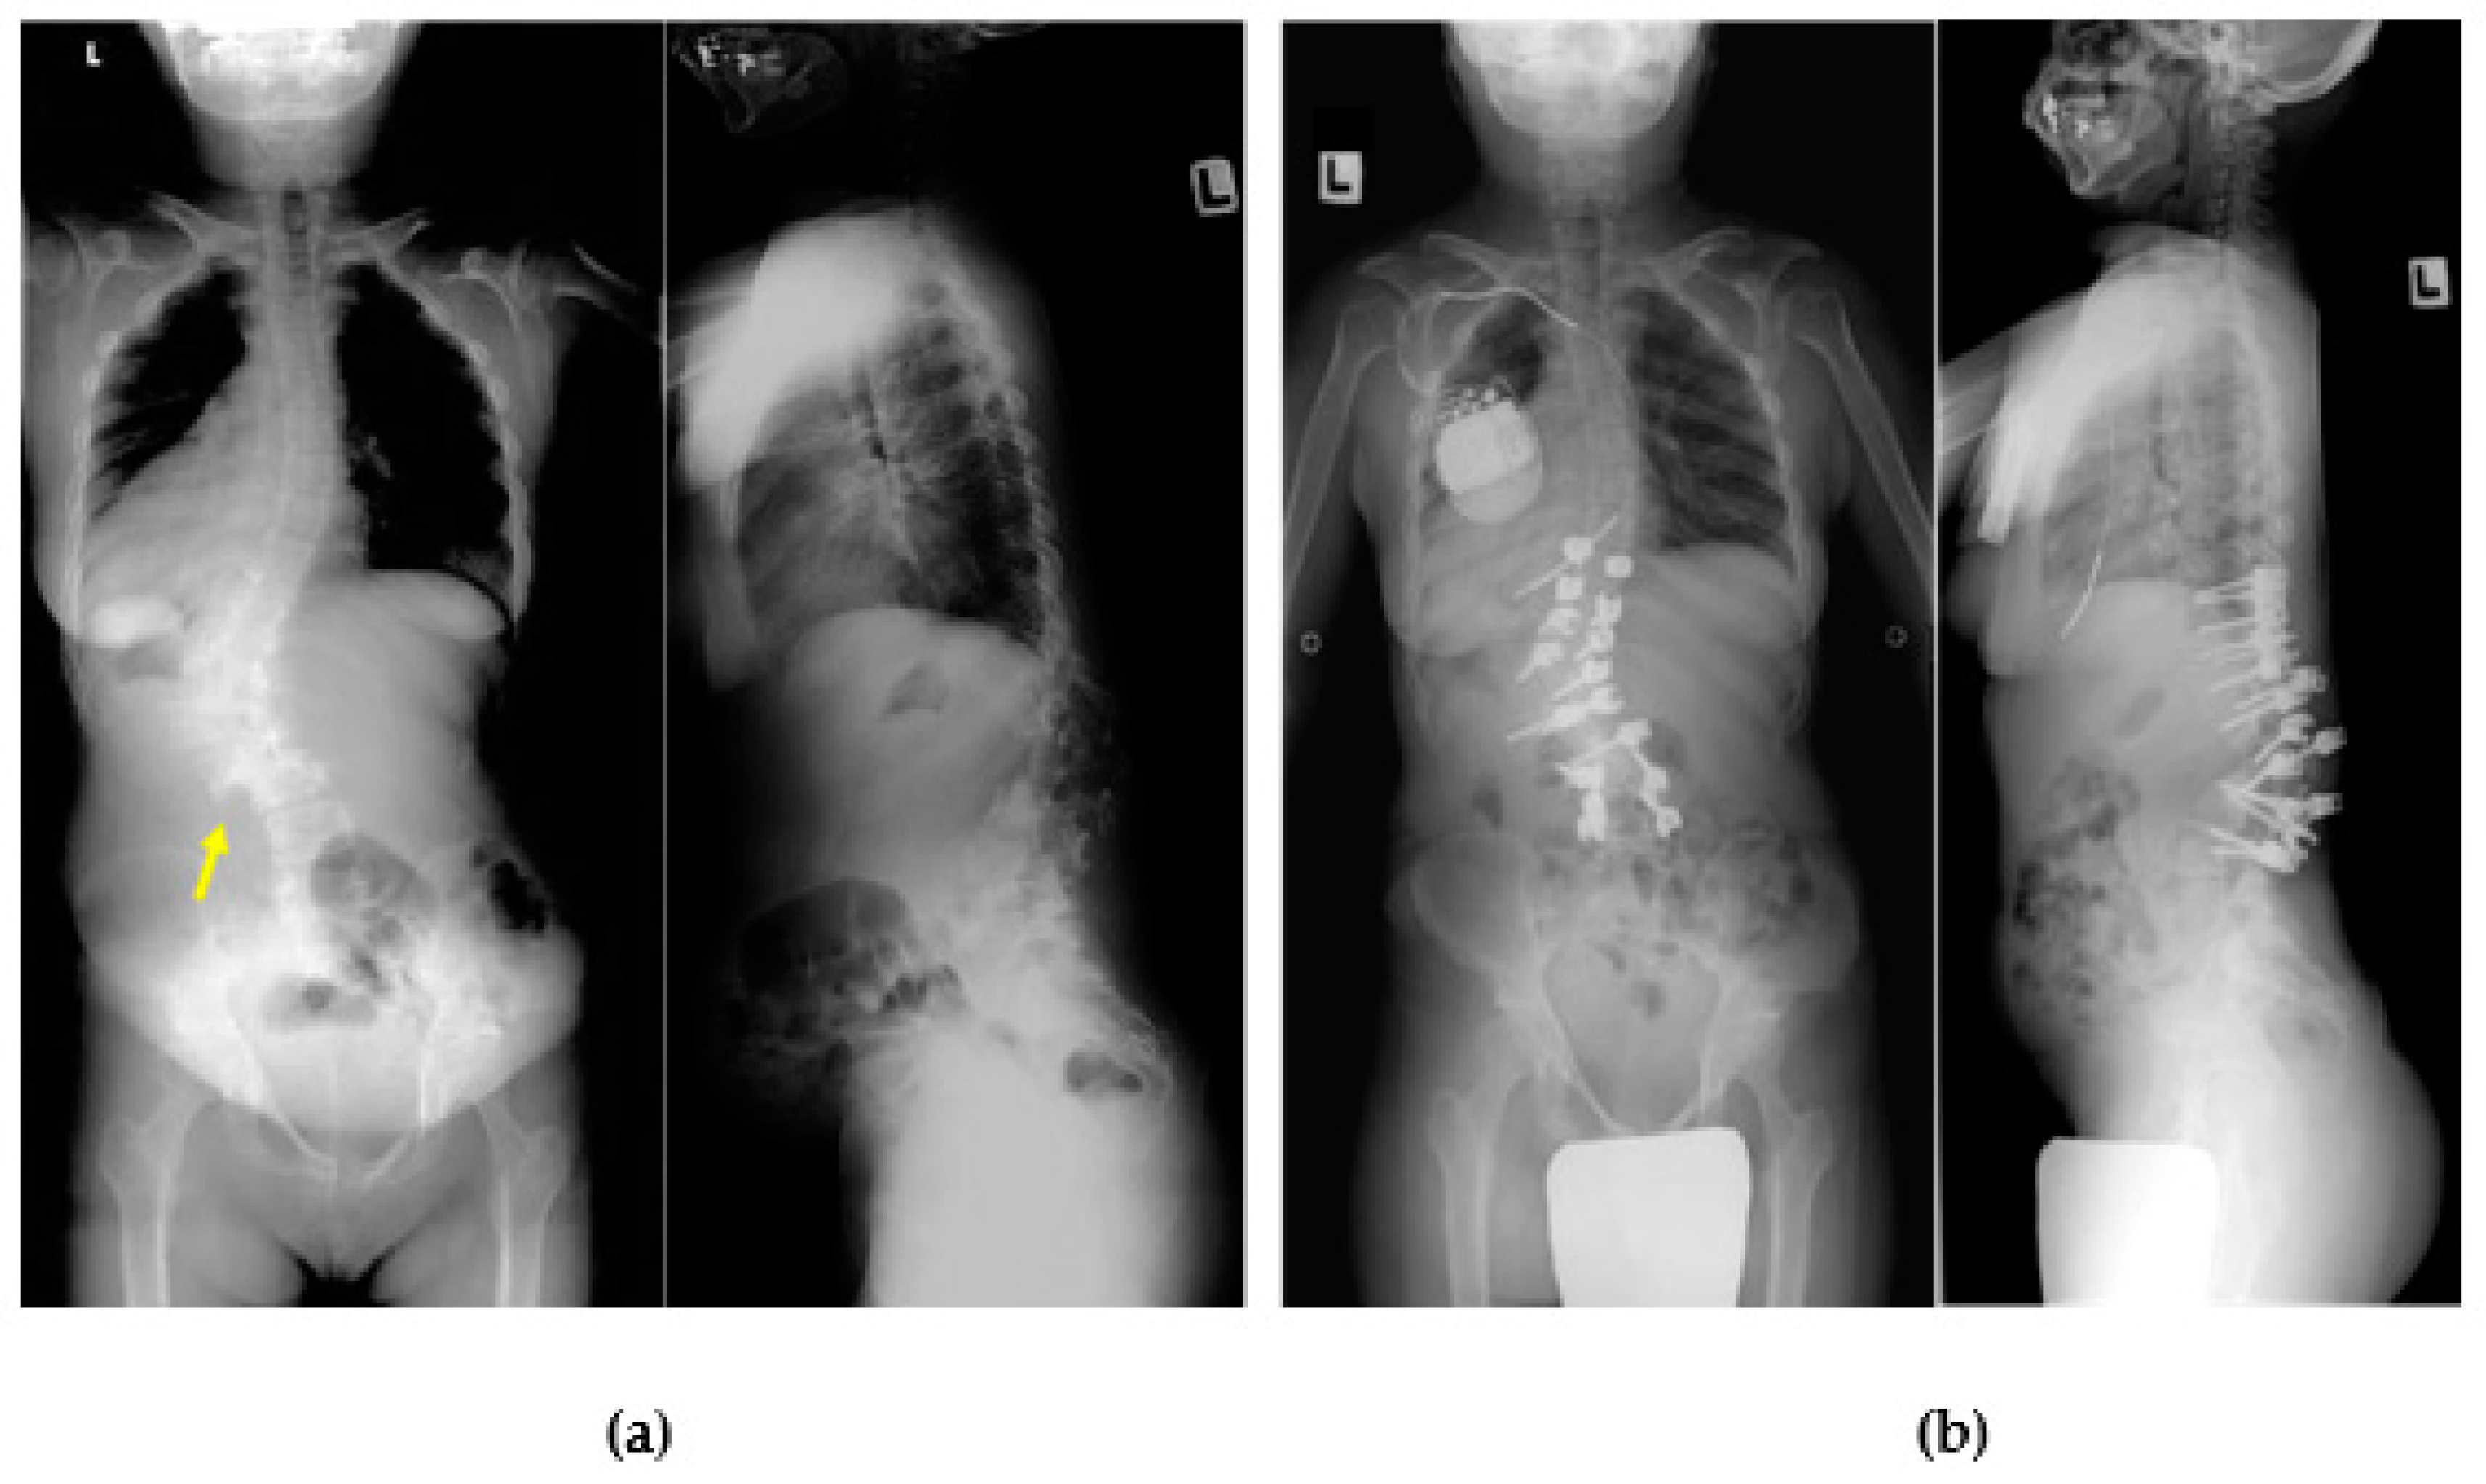

Progressive kyphosis with neurological deficit is commonly accepted by spine surgeons as a definitive indication for surgical intervention. Williams reported in a literature review of 58 patients with MPS (MPS I: 38 patients, MPS II: 3 patients, MPS IV: 9 patients, MPS VI: 8 patients), that perioperative neurological compromise associated with thoracolumbar kyphosis was observed only in MPS IV and VI (MPS IV: 5 patients, MPS VI: 2 patients). According to these results, the surgical indications for MPS I should be considered carefully because there are no long-term data describing the natural history of the progression curve as in other skeletal dysplasias, and there is also a lack of functional and quality of life assessments after thoracolumbar surgery [52]. Postoperative complications include death, neurological deficits, pseudarthrosis, infection, additional junctional deformity, and anesthesia-related problems. Additionally, perioperative thoracic spinal cord ischemia is a suspected cause of paraplegia [53]. We experienced cardiac arrest in a patient with MPS I during kyphoscoliosis surgery and had to discontinue the surgery after inserting the pedicle screws [54]. The patient was transferred to the intensive care unit and recovered completely after pacemaker insertion. The patient showed no progression of kyphoscoliosis 10 years postoperatively, but experienced moderate low-back pain. Surgeons should base the need for surgery not only on radiographical changes but also on the patient’s neurological function and quality of life (QoL), especially in patients with MPS I (Figure 8).

Figure 8.

Thoracolumbar kyphosis in attenuated MPS I. X-ray images of a 31-year-old woman with MPS I with low-back pain showing kyphoscoliosis and lateral slip of the lumbar spine (arrow) (a). Cardiac arrest occurred during surgery in the prone position, which required discontinuing surgery just after completing the pedicle screw insertion. The patient recovered fully without critical damage, although she required a pacemaker (b). More than 10 years postoperatively, the degree of kyphoscoliosis and low-back pain had not worsened.